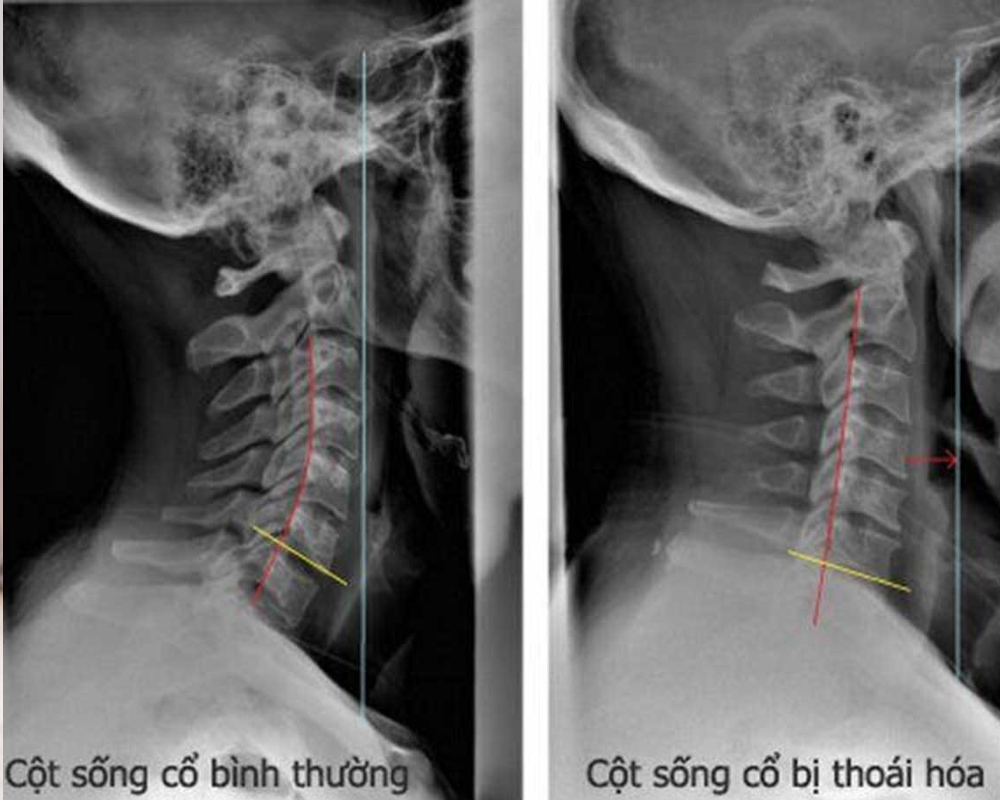

Hình ảnh thoái hóa cột sống cổ/lưng

Phát hiện sớm để điều trị thoái hóa cột sống thông qua những hình ảnh được chụp lại như:

- Thoái hóa cột sống cổ

Cột sống cổ gồm 7 đốt sống đầu tiên C1 - C7 nối từ xương sọ xuống.

Dấu hiệu nhận biết thoái hóa:

+ Hẹp đĩa đệm

+ Hình thành các gai xương

+ Dây thần kinh bị chèn ép